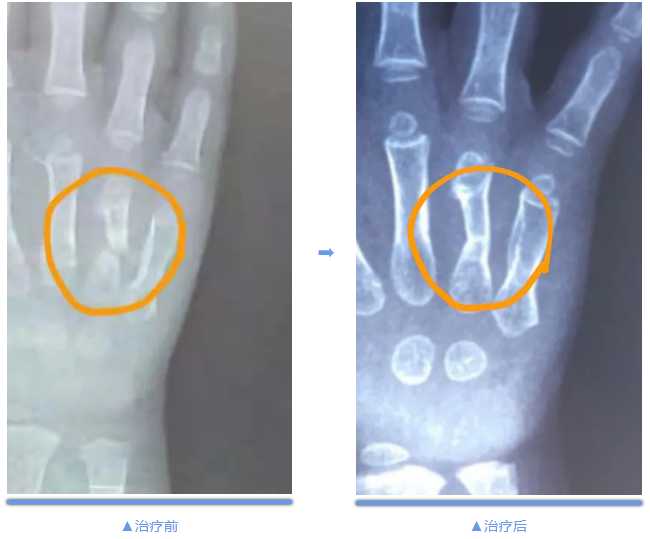

一位2岁的患儿,因车祸致右侧第四掌骨骨折,在当地医院行钢板内固定,3个月后拆除钢板,但骨折断端仍然没有任何愈合的迹象。骨科冲击波治疗中心自成立以来,虽然接诊数名骨折不愈合的患儿,但之前接诊的患儿最小年龄是6岁,而这例患儿只有2岁,创下了最小年龄的记录,而且国内外均未有治疗如此小患儿的经验。“年龄小”势必给治疗带来未知的困难。

患儿成功完成了两次冲击波治疗后,一个月复查,结果显示骨折断端已经临床愈合,无任何并发症。该患儿的成功治疗,再次显示了冲击波在骨折不愈合治疗中的“神奇”疗效。